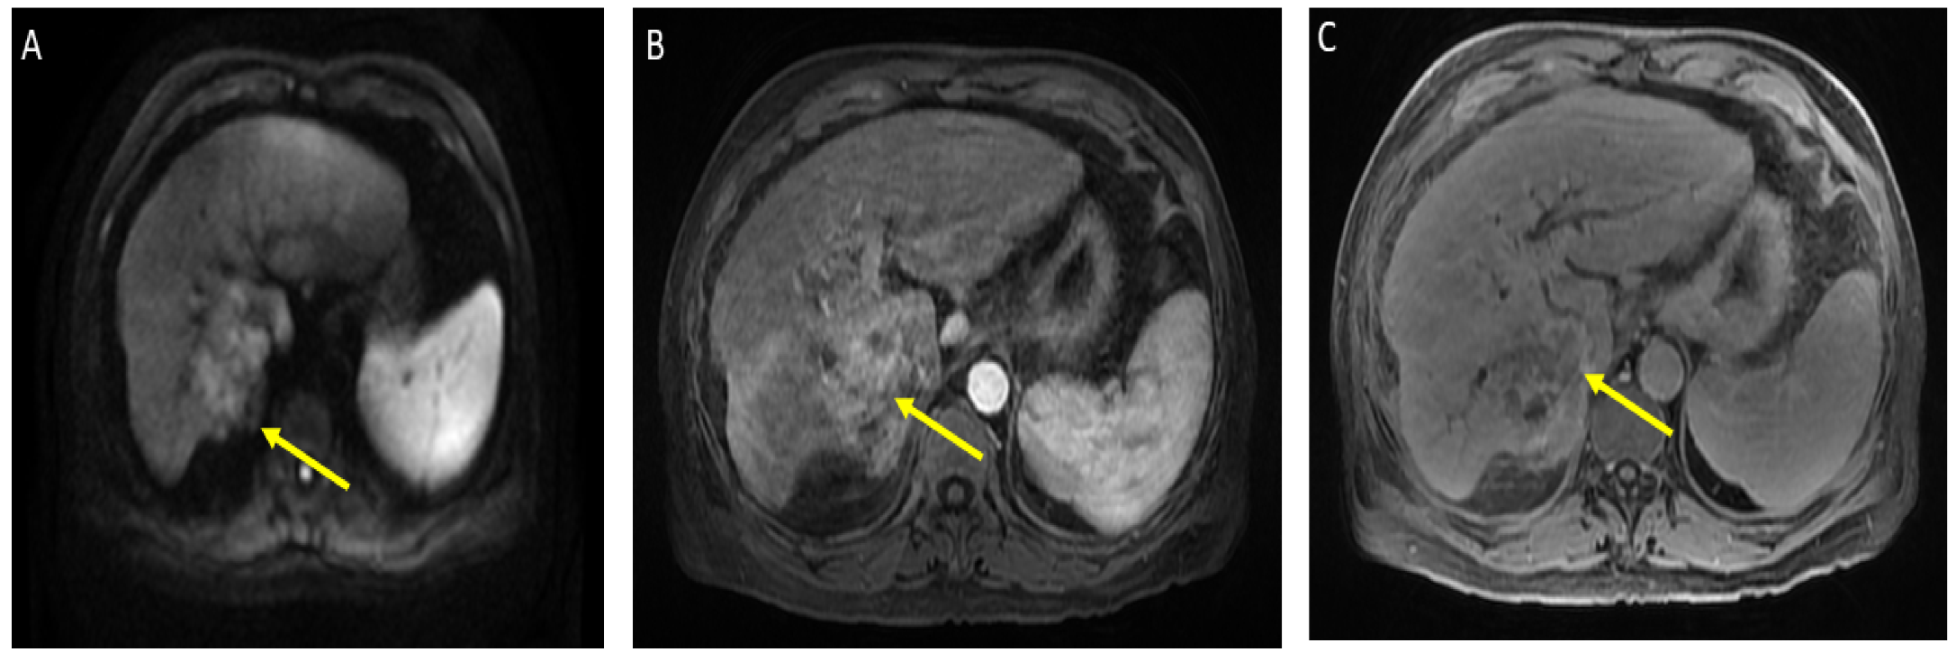

He was admitted for tumor evaluation which revealed a poorly differentiated, multifocal, grade 3 HCC. The Liver Imaging Reporting and Data System (LI-RADS) score was 5 (for arterial enhancement, washout, and size greater than 20 mm). Mild intrahepatic biliary dilatation secondary to mass effect was also noted. The tumor was confined to the liver with clear margins, no vascular invasion, normal regional lymph nodes by imaging criteria, and no evidence of distant metastasis, as can be seen in Figure 1.

Figure 1.

Magnetic resonance imaging of the abdomen. Limited by motion. Cirrhosis and splenomegaly were noted. Infiltrative segment 7 mass measures 6.5 × 4 cm. (A) Diffusion-weighted imaging (DWI) shows diffusion restriction of mass; (B) T1 with contrast shows vague arterial phase enhancement; (C) T1 post-contrast delayed phase imaging shows washout (captured at the diagnosis visit, and before the atezolizumab plus bevacizumab started).